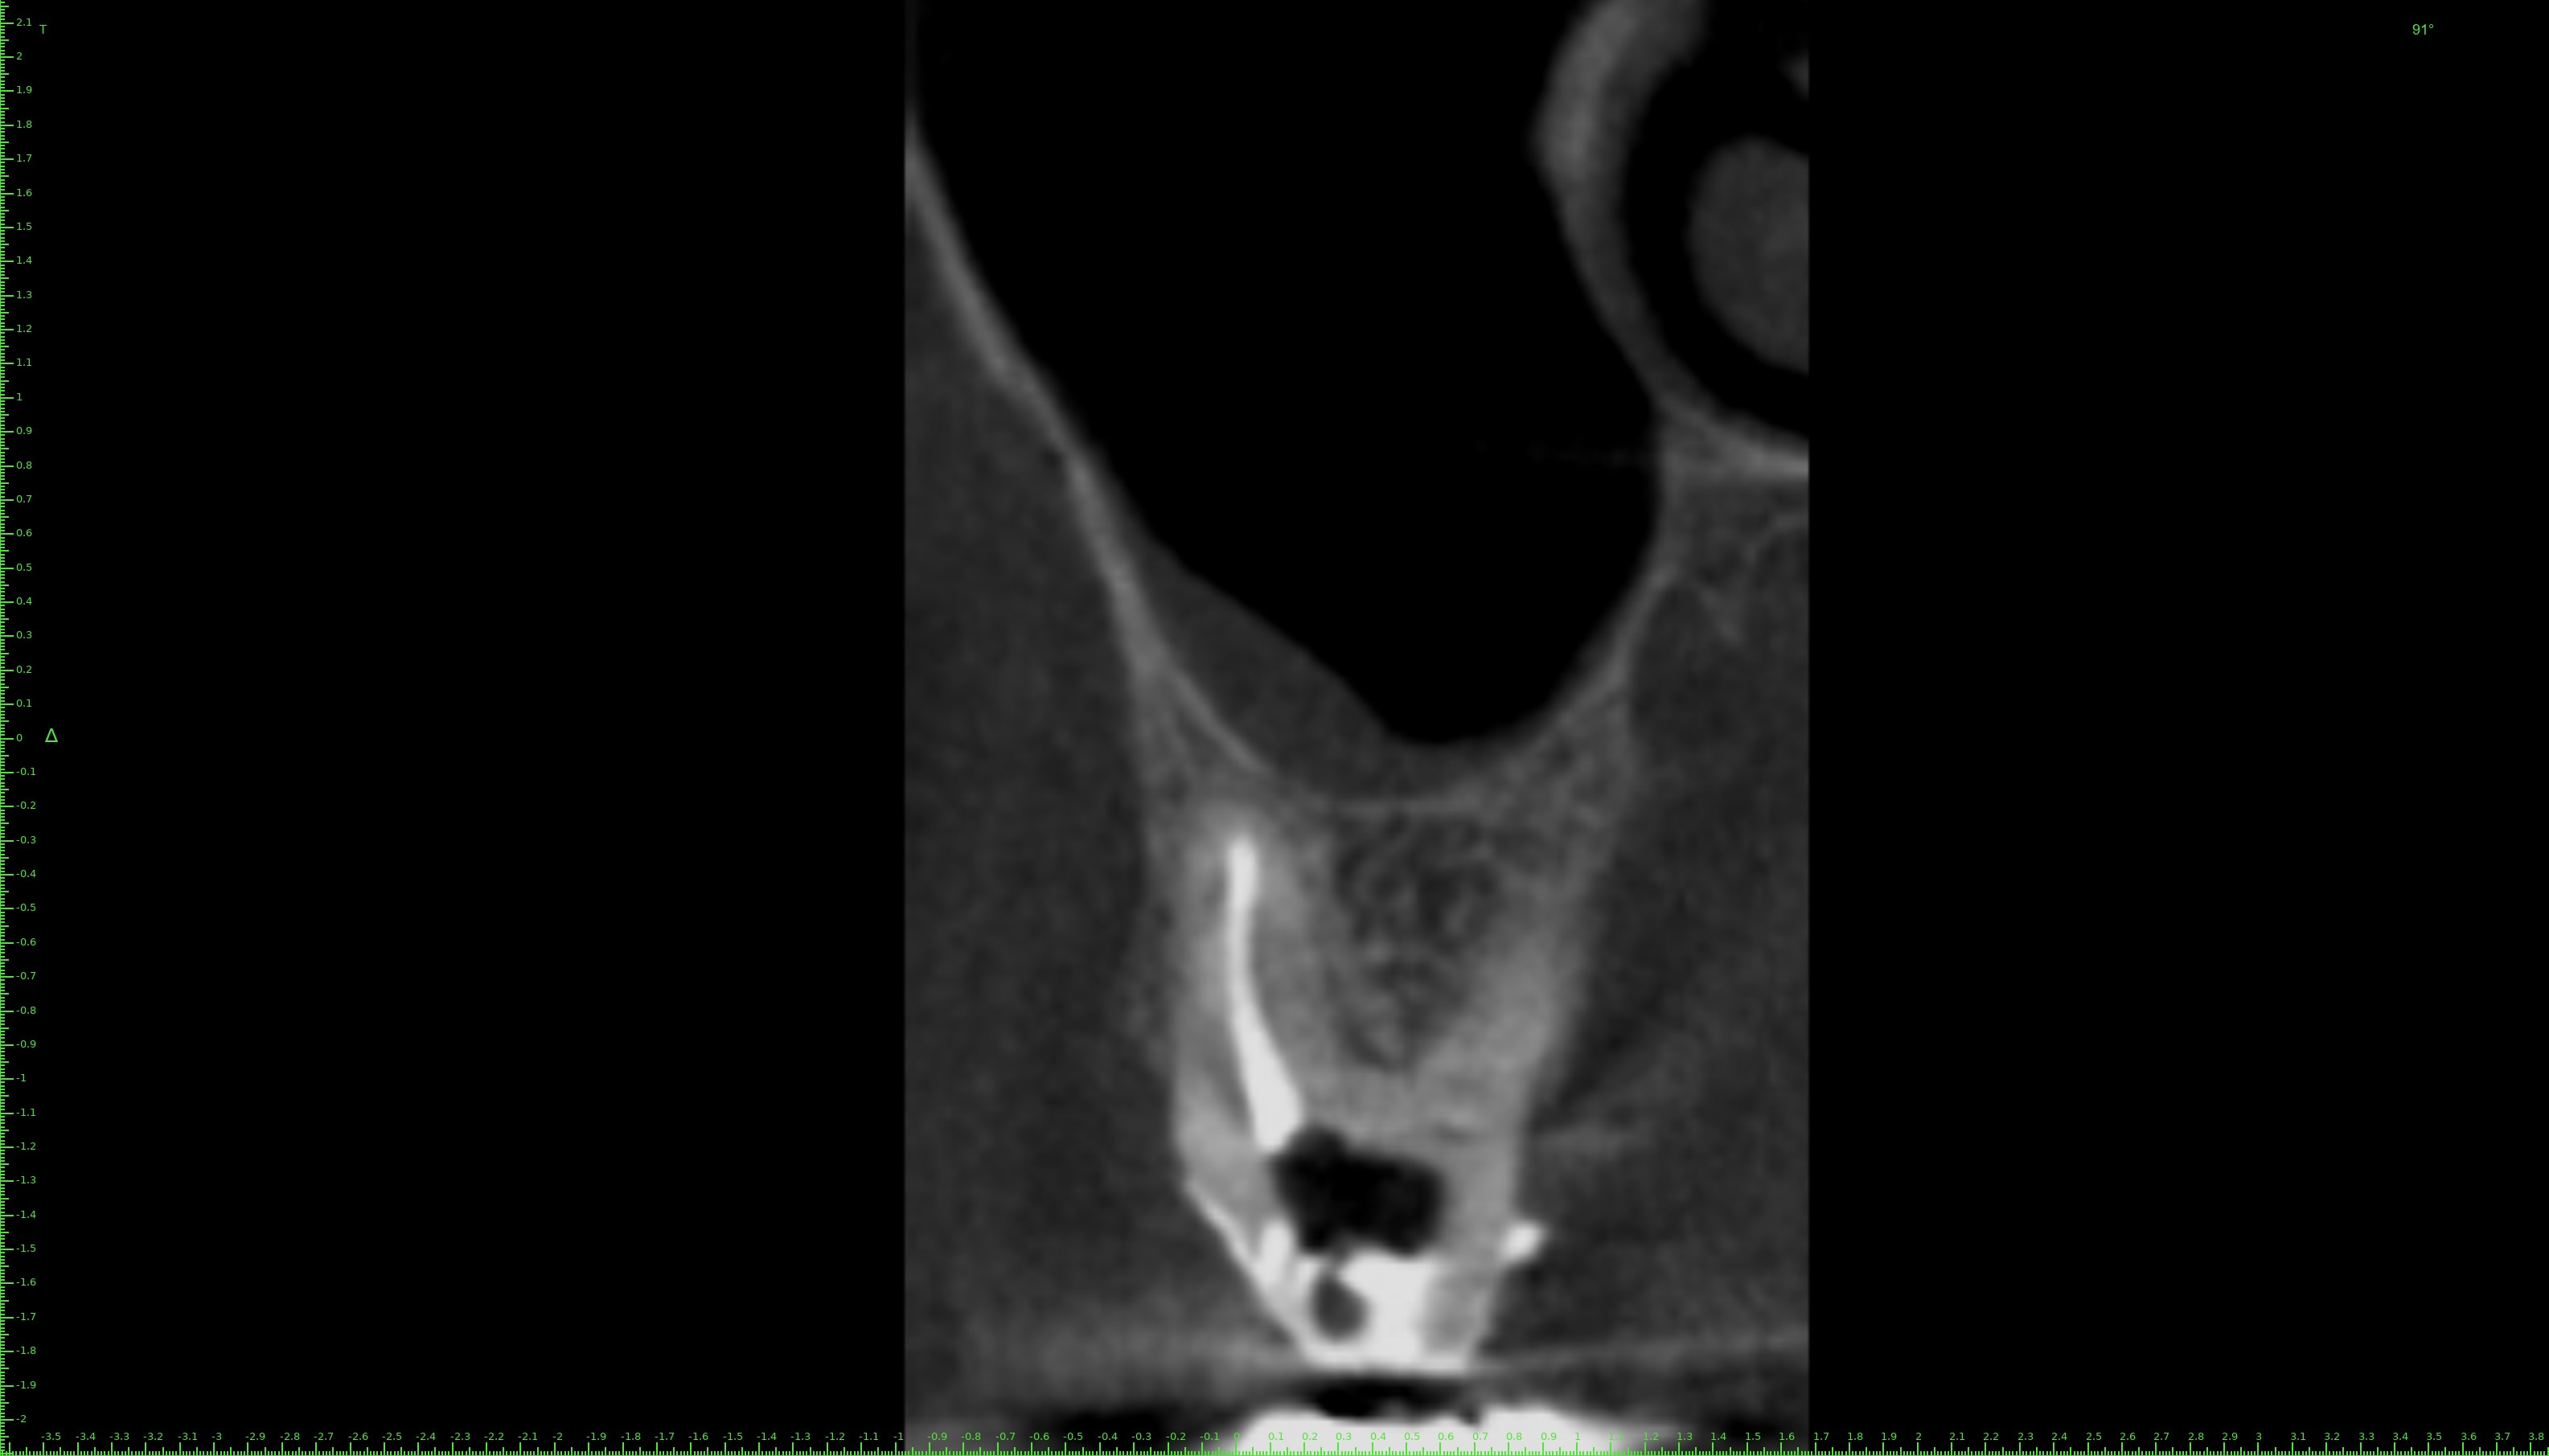

J'ai fait un conebeam de la 26.

L'obturation des racines est correcte, il y a juste une petite image apicale au niveau de la racine palatine avec un léger dépassement de pâte.

Pas de coupes horizontales ?

Le MV2 non obturé ici peut parfois, selon sa configuration, causer des douleurs variées.

Je peux me tromper, les coupes ne sont pas idéales pour conclure ☝️

Pour répondre à Dentarue: je viens de faire des coupes horizontale et centrées sur la racine vestibulaire en tournant autour d'un potentiel MV2. La gutta et le ciment font un joli artefact radio donc ce n'est pas concluant.

On le voit très bien sur ta 3d.

Aucune gloire, on ne voit que ça.

Chercher une deuxième entrée en vestibulaire quand on voit sur cette coupe et sur la coupe horizontale que c’est le palatin qui n’est pas obturé, … les mots me manquent.

Il cherche en vestibulaire de MV mais c’est en palatin de MV qu’il fallait chercher, cela me semblait aller sans dire ☝️

Tout est sur la 3d.

Le MV2 n’est pas très proche de la furcation mais plutôt plus mésial que le MV1. Il est très visible à la radio et ne doit pas être bien compliqué à traiter, mais pour ça il faut s’en donner les moyens et ça commence par la digue.

Tu nous dis qu’il n’y a pas de MV2 et tu nous montres des coupes où il saute aux yeux puis tu vois la patiente entre deux pour désobturer MV1 sans digue… et laisser MV2 non traité…

Il est plus mésial.

Si ce qu’on voit est le MV1 désobturé, le MV2 est à peu de chose près là où est ta flèche verte. Son entrée est souvent plus apicale. Le trouver est une chose, le négocier une autre, souvent bien chronophage.